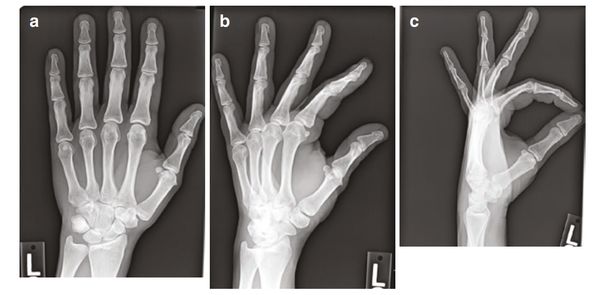

Основной метод диагностики — рентгенография в нескольких проекциях, как правило в прямой и боковой, но дополнительно могут делать косую (особенно для пальцев ног). Рентген может показать наличие перелома, его локализацию и линию, характер и степень смещения отломков, а также возможные осколки.

![Рентген кисти в заднепередней, косой и боковой проекциях [8] Рентген кисти в заднепередней, косой и боковой проекциях [8]](/media/bolezny/perelom-palca/rentgen-kisti-v-zadneperednyay-kosoy-i-bokovoy-proekciyah-8_s.jpeg?dummy=1777377925978)

Рентген кисти в заднепередней, косой и боковой проекциях [8]